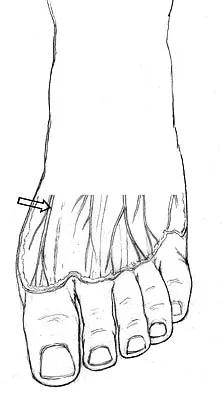

The dorsal digital cutaneous nerve of the great toe shown in Figure 8 is a branch of what nerve?

Explanation